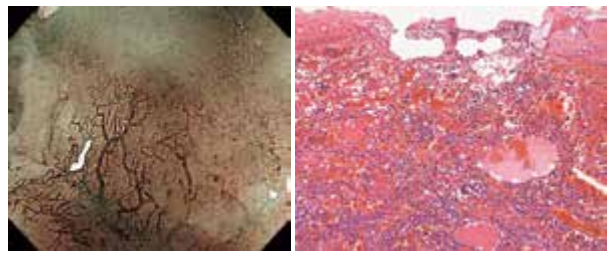

上图:通过HE染色,可以看到在组织间质中核质比(N/C)较高的细胞集聚。

下图:通过免疫组化染色,突触素(synaptophysin)和嗜铬粒蛋白A(chromogranin A)染色为阳性,疑为神经内分泌癌。

NBI下放大观察到的R型微细血管从表层到深处,在组织学上显示逐渐变粗的倾向。